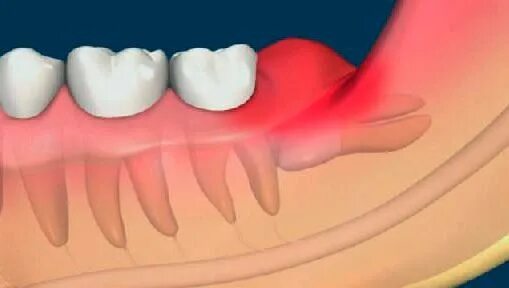

Болит вся челюсть и все зубы